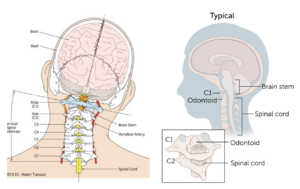

頭痛とめまいを引き起こした頭蓋頸椎の変位